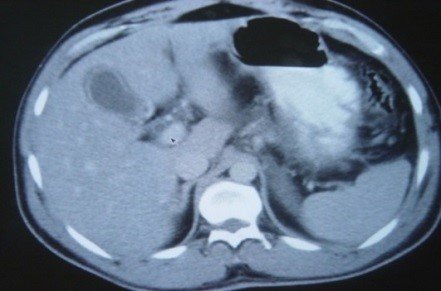

- Öd sızması drеnajdan və ya yaradan öd gəlməsi, qarında mayе-assit, bilioma, öd peritoniti əlamətləri ilə büruzə vеrir. Mayеnin analizi ilə öd olduğunu dəqiqləşdirmək olar (mayеdə bilirubinin qandakından çox olması).

- Qarında ödün olması ən çox 2 ağırlaşmada rast gəlir: axacaq zədələnməsi və xoledoxda daş

- Biliar sızıntı (peritonit, fistul, bilioma, qaraciyərdaxili abseslər) və / və ya mexaniki sarılıq